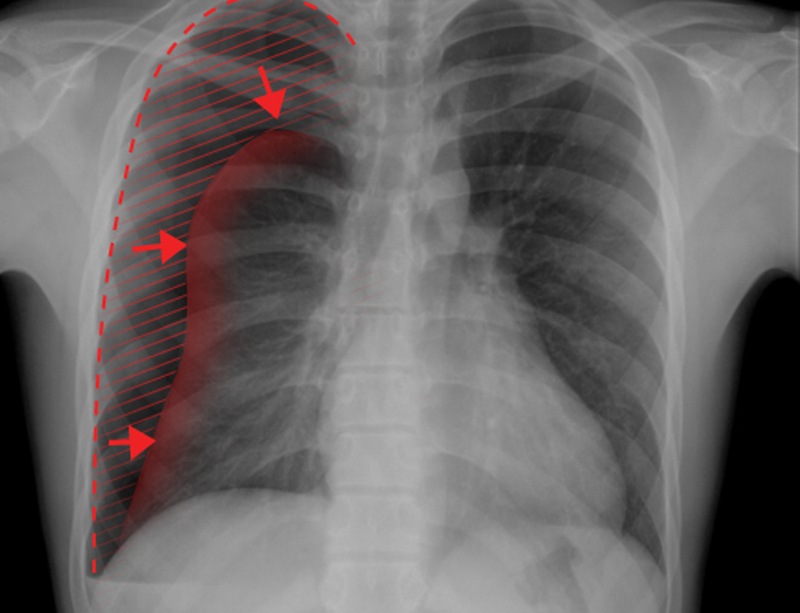

4. 기흉

공기가 폐에서 나와서 폐와 흉벽사이에 들어갈때를 기흉이라 합니다.

기흉은 호흡할때 폐를 완전히 팽창하지 못하게 만듭니다. 이는 오른쪽 가슴통증을 유발할 수 있습니다.